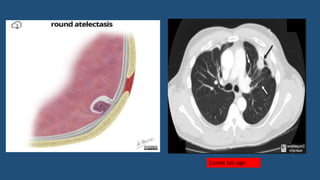

Rounded atelactasis

• Represents focal, collapsed, and often folded lung.

• Appear as mass or mass-like consolidation and are usually several cms in

diameter.

• 4 findings must be present to make absolute diagnosis

• Ipsilateral pleural thickening or effusion

• Significant contact between the lung lesion and the abnormal pleural surface

• Comet tail sign: Bending or bowing of adjacent bronchi and arteries toward the

edge of the area of rounded atelectasis.

• Volume loss in the lobe in which there is opacity.

Comet tail sign